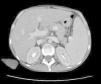

Cultures of blood, urine, stool and bone marrow were negative for common bacteria, typical and atypical mycobacteria and fungi. Thoracentesis reported an uncomplicated exudate. Computed tomography with contrast (oral and IV) of the head, neck and pelvis were normal; the scan showed the presence of a bibasal pleural effusion, and the abdomen (Fig. 1) showed homogeneous hepatomegaly (230mm of longitudinal diameter) and splenomegaly (200mm of longitudinal diameter). Hepatic vessels on an eco Doppler ultrasound showed dilation of the portal vein (14mm in diameter) with no evidence of thrombosis. Upper gastrointestinal fiberoptic endoscopy ruled out the presence of esophageal varices.